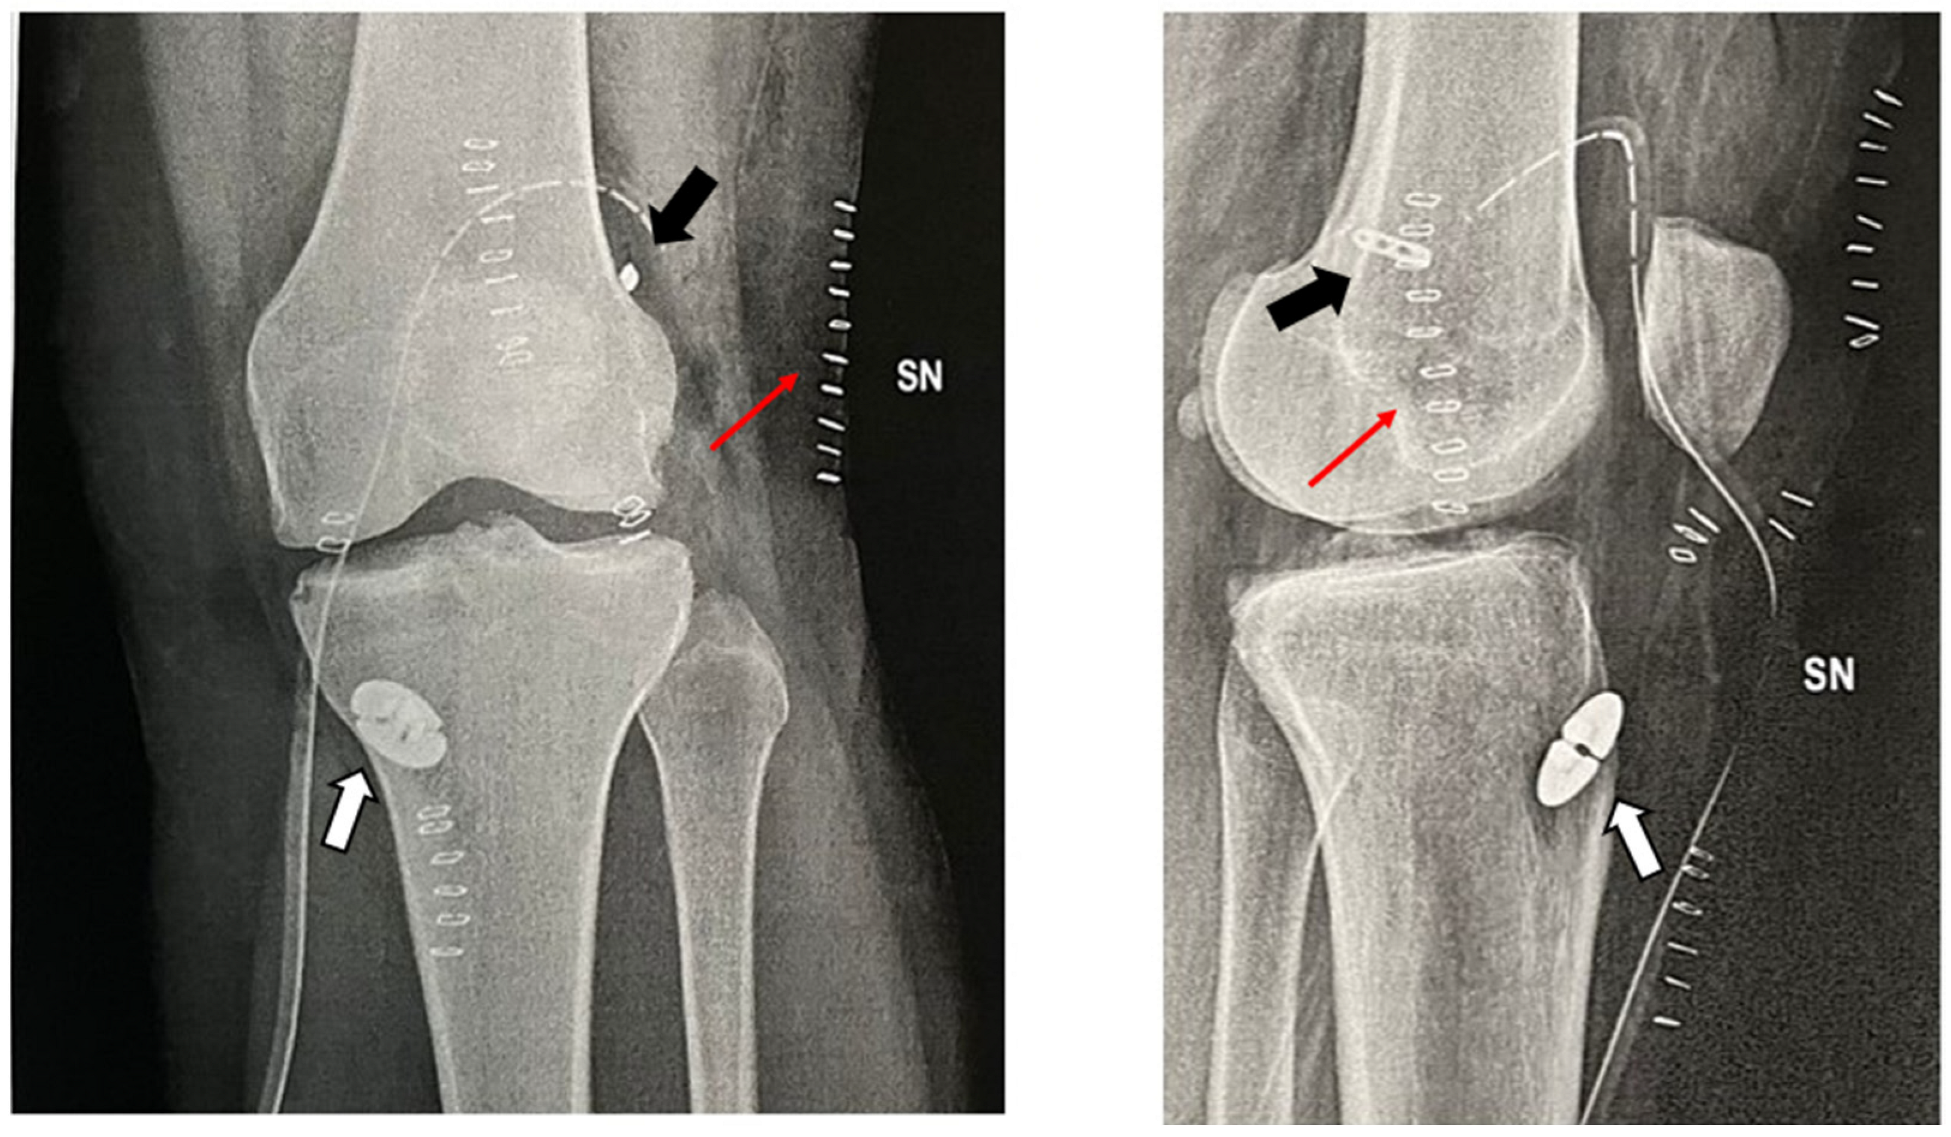

Post-operatively, full-weight-bearing as tolerated and immediate ROM and muscle-strengthening exercises are allowed from the first post-operative day. The addition of the lateral tenodesis does not alter in any way the standard ACL reconstruction post-operative regimen, weight-bearing allowance or the type of physiotherapy protocol, all of which are predominantly influenced by additional procedures at the meniscal level (e.g., selective meniscectomy, sutures, root reinsertion) or at the cartilage level (e.g., microfractures, OATS, AMIC). Post-operative X-rays are shown (Figure 6).

Figure 6.

Post-operative X-rays. The surgical drainage is still in place, and the graft is fixed with two adjustable loop suspensory devices (black arrow) and a dedicated button on the tibial side (white arrow). On the lateral projection, only the skin staples (thin red arrow) can be appreciated at the level of the ITB harvesting site, since no additional hardware was used to fix the ITB strip.